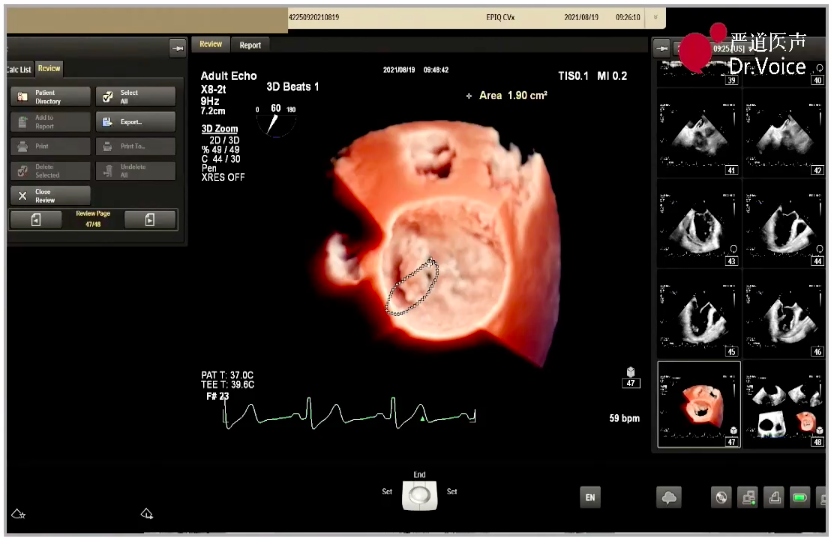

瓣夹目标夹闭角度

初次夹闭时二尖瓣前瓣夹闭部分偏少,调整位置后尝试夹闭,超声显示瓣夹一侧出现少量反流;松开瓣夹后再次调整位置,准确捕获并充分夹闭二尖瓣瓣叶,完成经导管缘对缘修复。

最终夹闭后的超声图像

二尖瓣夹释放后,超声显示反流几近消失,二尖瓣前向峰值流速1.2m/s,平均跨瓣压差3mmHg。患者各项生理指标正常,手术顺利完成,手术操作耗时约120 min。